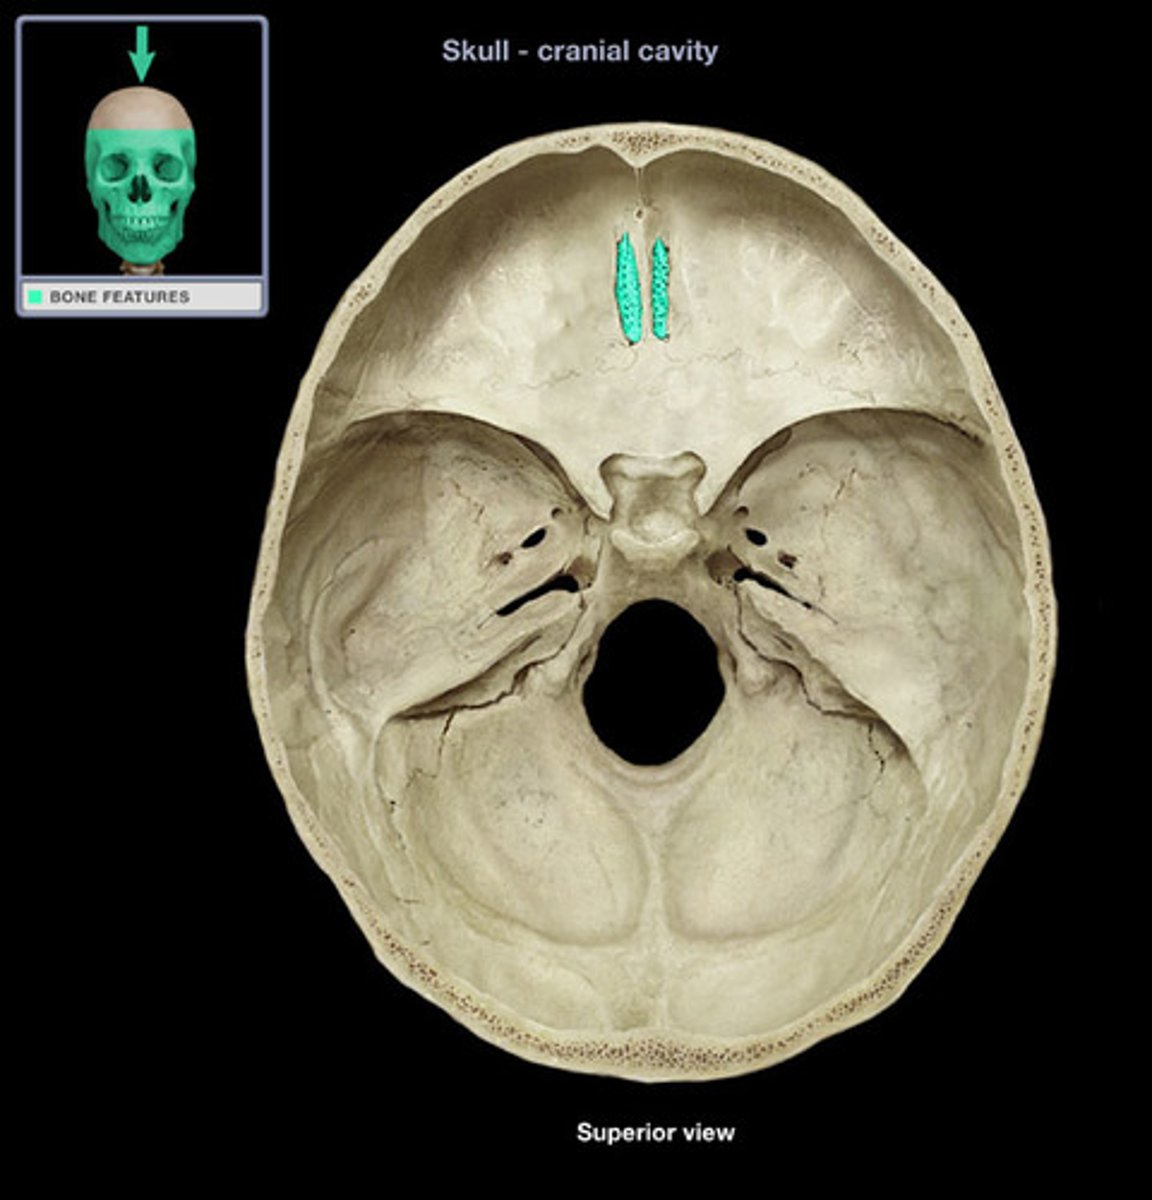

Cribriform plate

Horizontal bone structure with olfactory foramina.

Anterior ethmoid foramen

Opening for nerves and vessels at the front.

Posterior ethmoid foramen

Opening for nerves and vessels at the back.

Ethmoid air cells

Air-filled spaces within the ethmoid bone.